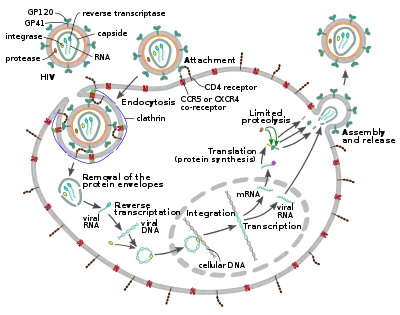

The HIV replication cycle

Entry to the cell

Mechanism of viral entry: 1. Initial interaction between gp120 and CD4. 2. Conformational change in gp120 allows for secondary interaction with CXCR4. 3. The distal tips of gp41 are inserted into the cellular membrane. 4. gp41 undergoes significant conformational change; folding in half and forming coiled-coils. This process pulls the viral and cellular membranes together, fusing them.

The HIV virion enters macrophages and CD4+ T cells by the adsorption of glycoproteins on its surface to receptors on the target cell followed by fusion of the viral envelope with the target cell membrane and the release of the HIV capsid into the cell.[58][59]

Entry to the cell begins through interaction of the trimeric envelope complex (gp160 spike) on the HIV viral envelope and both CD4 and a chemokine co-receptor (generally either CCR5 or CXCR4, but others are known to interact) on the target cell surface.[58][59] Gp120 binds to integrin α4β7 activating LFA-1, the central integrin involved in the establishment of virological synapses, which facilitate efficient cell-to-cell spreading of HIV-1.[60] The gp160 spike contains binding domains for both CD4 and chemokine receptors.[58][59]

The first step in fusion involves the high-affinity attachment of the CD4 binding domains of gp120 to CD4. Once gp120 is bound with the CD4 protein, the envelope complex undergoes a structural change, exposing the chemokine receptor binding domains of gp120 and allowing them to interact with the target chemokine receptor.[58][59] This allows for a more stable two-pronged attachment, which allows the N-terminal fusion peptide gp41 to penetrate the cell membrane.[58][59] Repeat sequences in gp41, HR1, and HR2 then interact, causing the collapse of the extracellular portion of gp41 into a hairpin shape. This loop structure brings the virus and cell membranes close together, allowing fusion of the membranes and subsequent entry of the viral capsid.[58][59]

After HIV has bound to the target cell, the HIV RNA and various enzymes, including reverse transcriptase, integrase, ribonuclease, and protease, are injected into the cell.[58] During the microtubule-based transport to the nucleus, the viral single-strand RNA genome is transcribed into double-strand DNA, which is then integrated into a host chromosome.

HIV-1 entry, as well as entry of many other retroviruses, has long been believed to occur exclusively at the plasma membrane. More recently, however, productive infection by pH-independent, clathrin-mediated endocytosis of HIV-1 has also been reported and was recently suggested to constitute the only route of productive entry.[63][64][65][66][67]